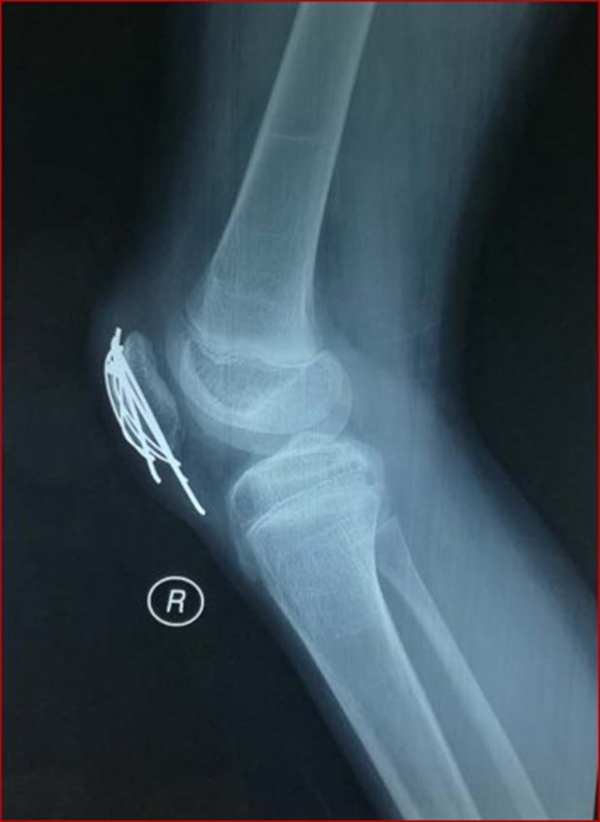

图1 受伤当时X线片

图2 受伤3周X线片